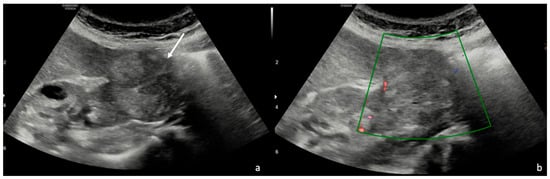

3.1. Ultrasound (US)

| Features | % | n. | p Value |

| 92.6% | 25 | p < 0.05 |

| 7.4% | 2 | p > 0.05 |

| 85.2% | 23 | p < 0.05 |

| 14.8% | 4 | p > 0.05 |

| US Features | % | n. | p Value |

| 70.3% | 19 | p < 0.05 |

| 11.1% | 3 | |

| 18.5% | 5 | p > 0.05 |

| 37.0% | 10 | p > 0.05 |